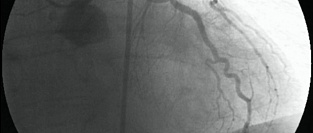

Незначимые поражения коронарных артерий и частота инфарктов миокарда

Результаты крупного анализа данных пациентов, получающих медицинскую помощь в учреждениях системы Ми...

11.11.2014 8496 #ИБС #ишемическая болезнь сердца #коронарография #инфаркт миокарда